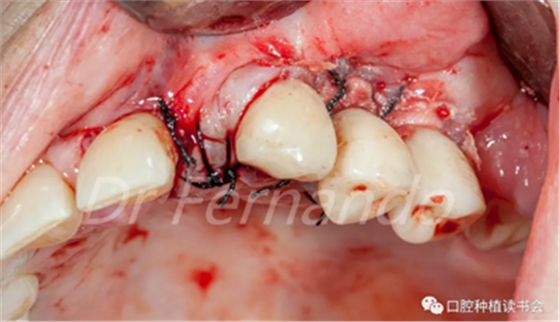

在骨粉上方覆蓋 Osgide? 可吸收膠原膜(Curasan?-科盧森) ,用絲線嚴密關(guān)閉傷口(圖 22 )

圖22 植骨區(qū)覆蓋可吸收膠原膜,關(guān)閉創(chuàng)口

患者術(shù)后接受了8天系統(tǒng)的抗生素、鎮(zhèn)痛和抗炎治療。術(shù)后15天種植體周圍黏膜恢復(fù)健康(圖 23 )。

圖23 術(shù)后15天術(shù)區(qū)恢復(fù)健康